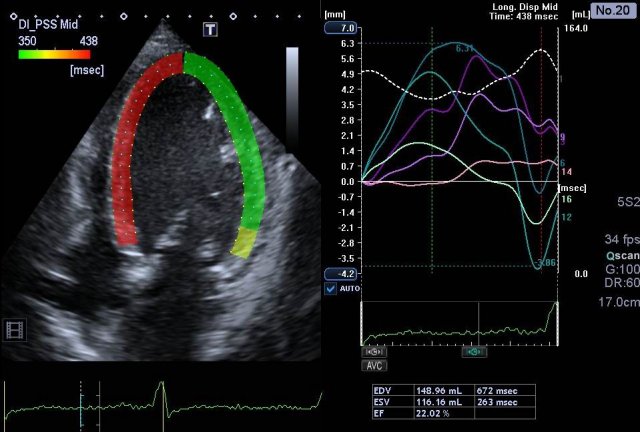

Linksschenkelblock im 2D-Strain

Herzmuskelschwäche-Vektoranalyse